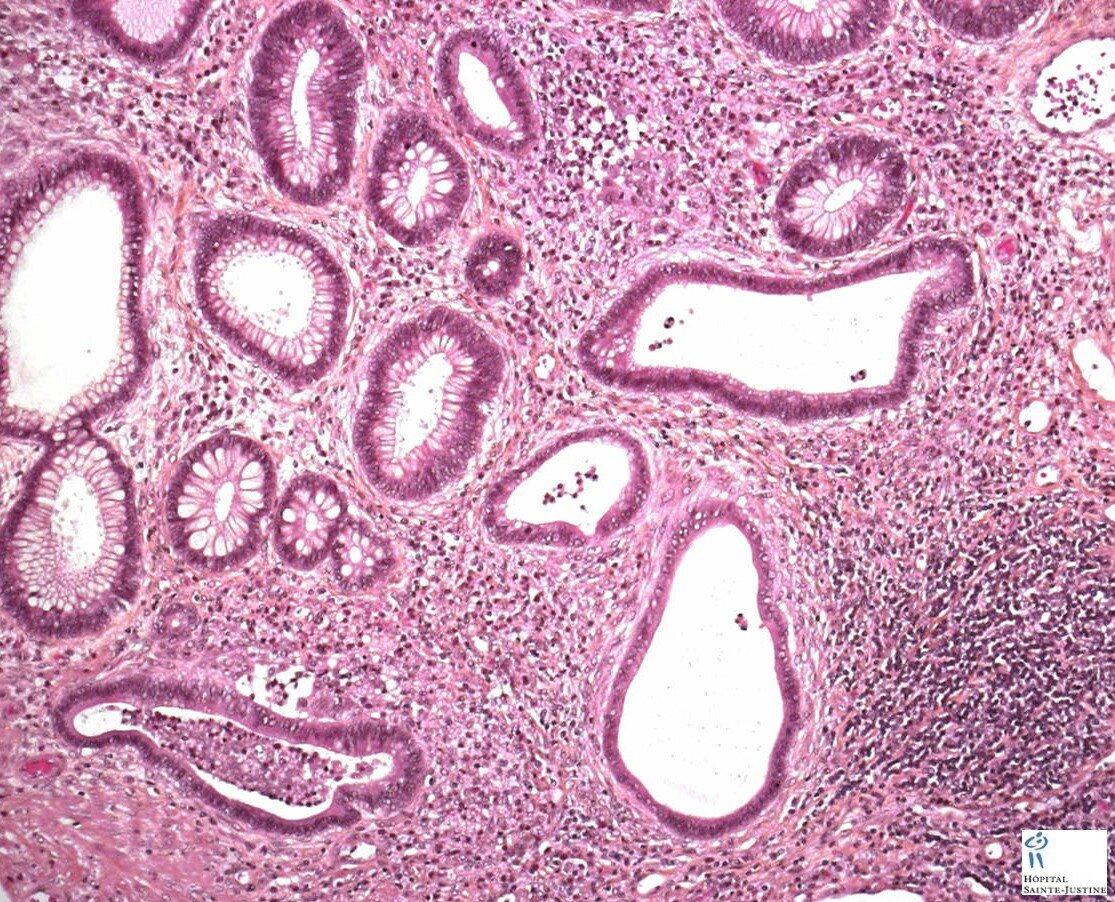

multiple digestive juvenile polyps